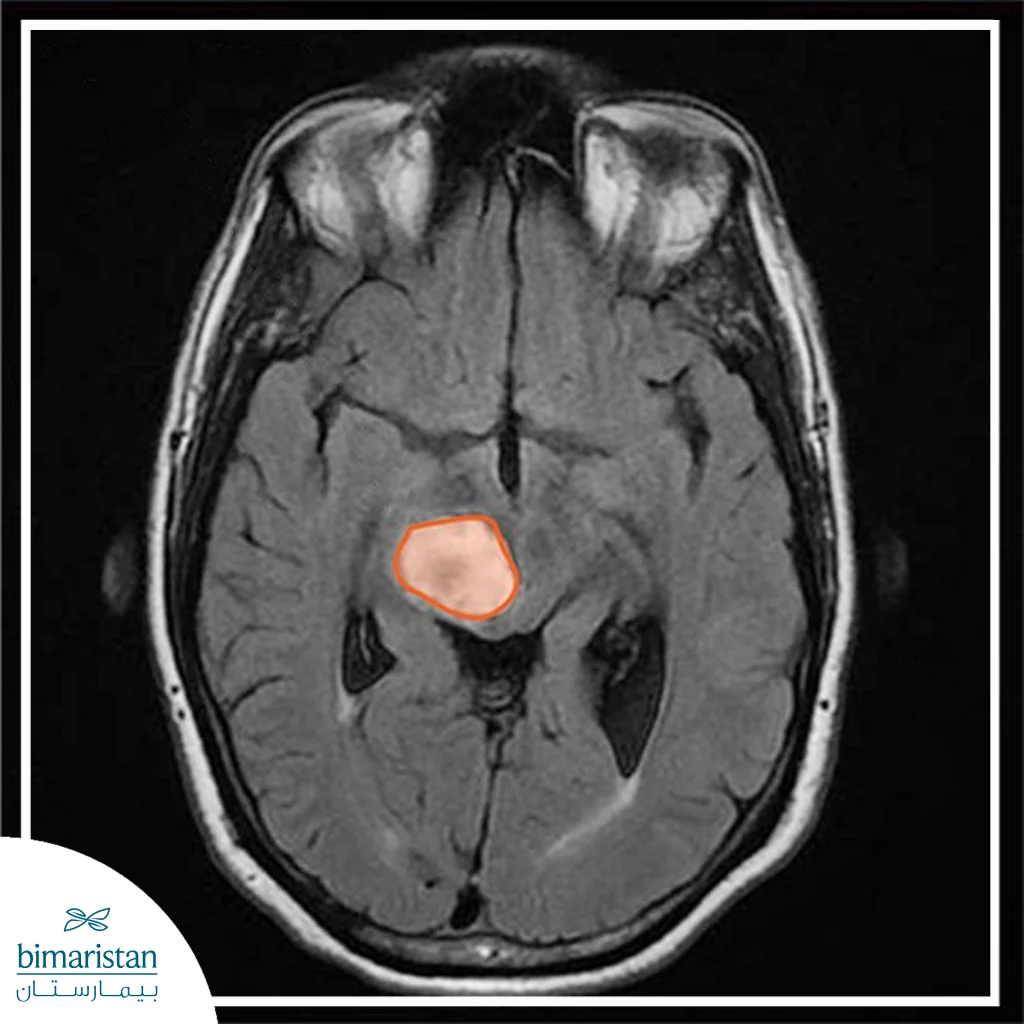

- اختبارات التصوير: يساعد التصوير بالرنين المغناطيسي (MRI) على الكشف عن ورم الدماغ.

أورام الدماغ (الورم الدماغي) هي وجود كتلة أو نمو للخلايا الشاذة (الغير طبيعية) في الدماغ. هناك أنواع مختلفة من أورام الدماغ:

تختلف سرعة نمو أورام الدماغ بصورة كبيرة، حيث يُحدِّد معدَّل النمو وكذلك موضع وحجم وَرَم المخ مدى تأثيره على وظيفة جهازكَ العصبي.